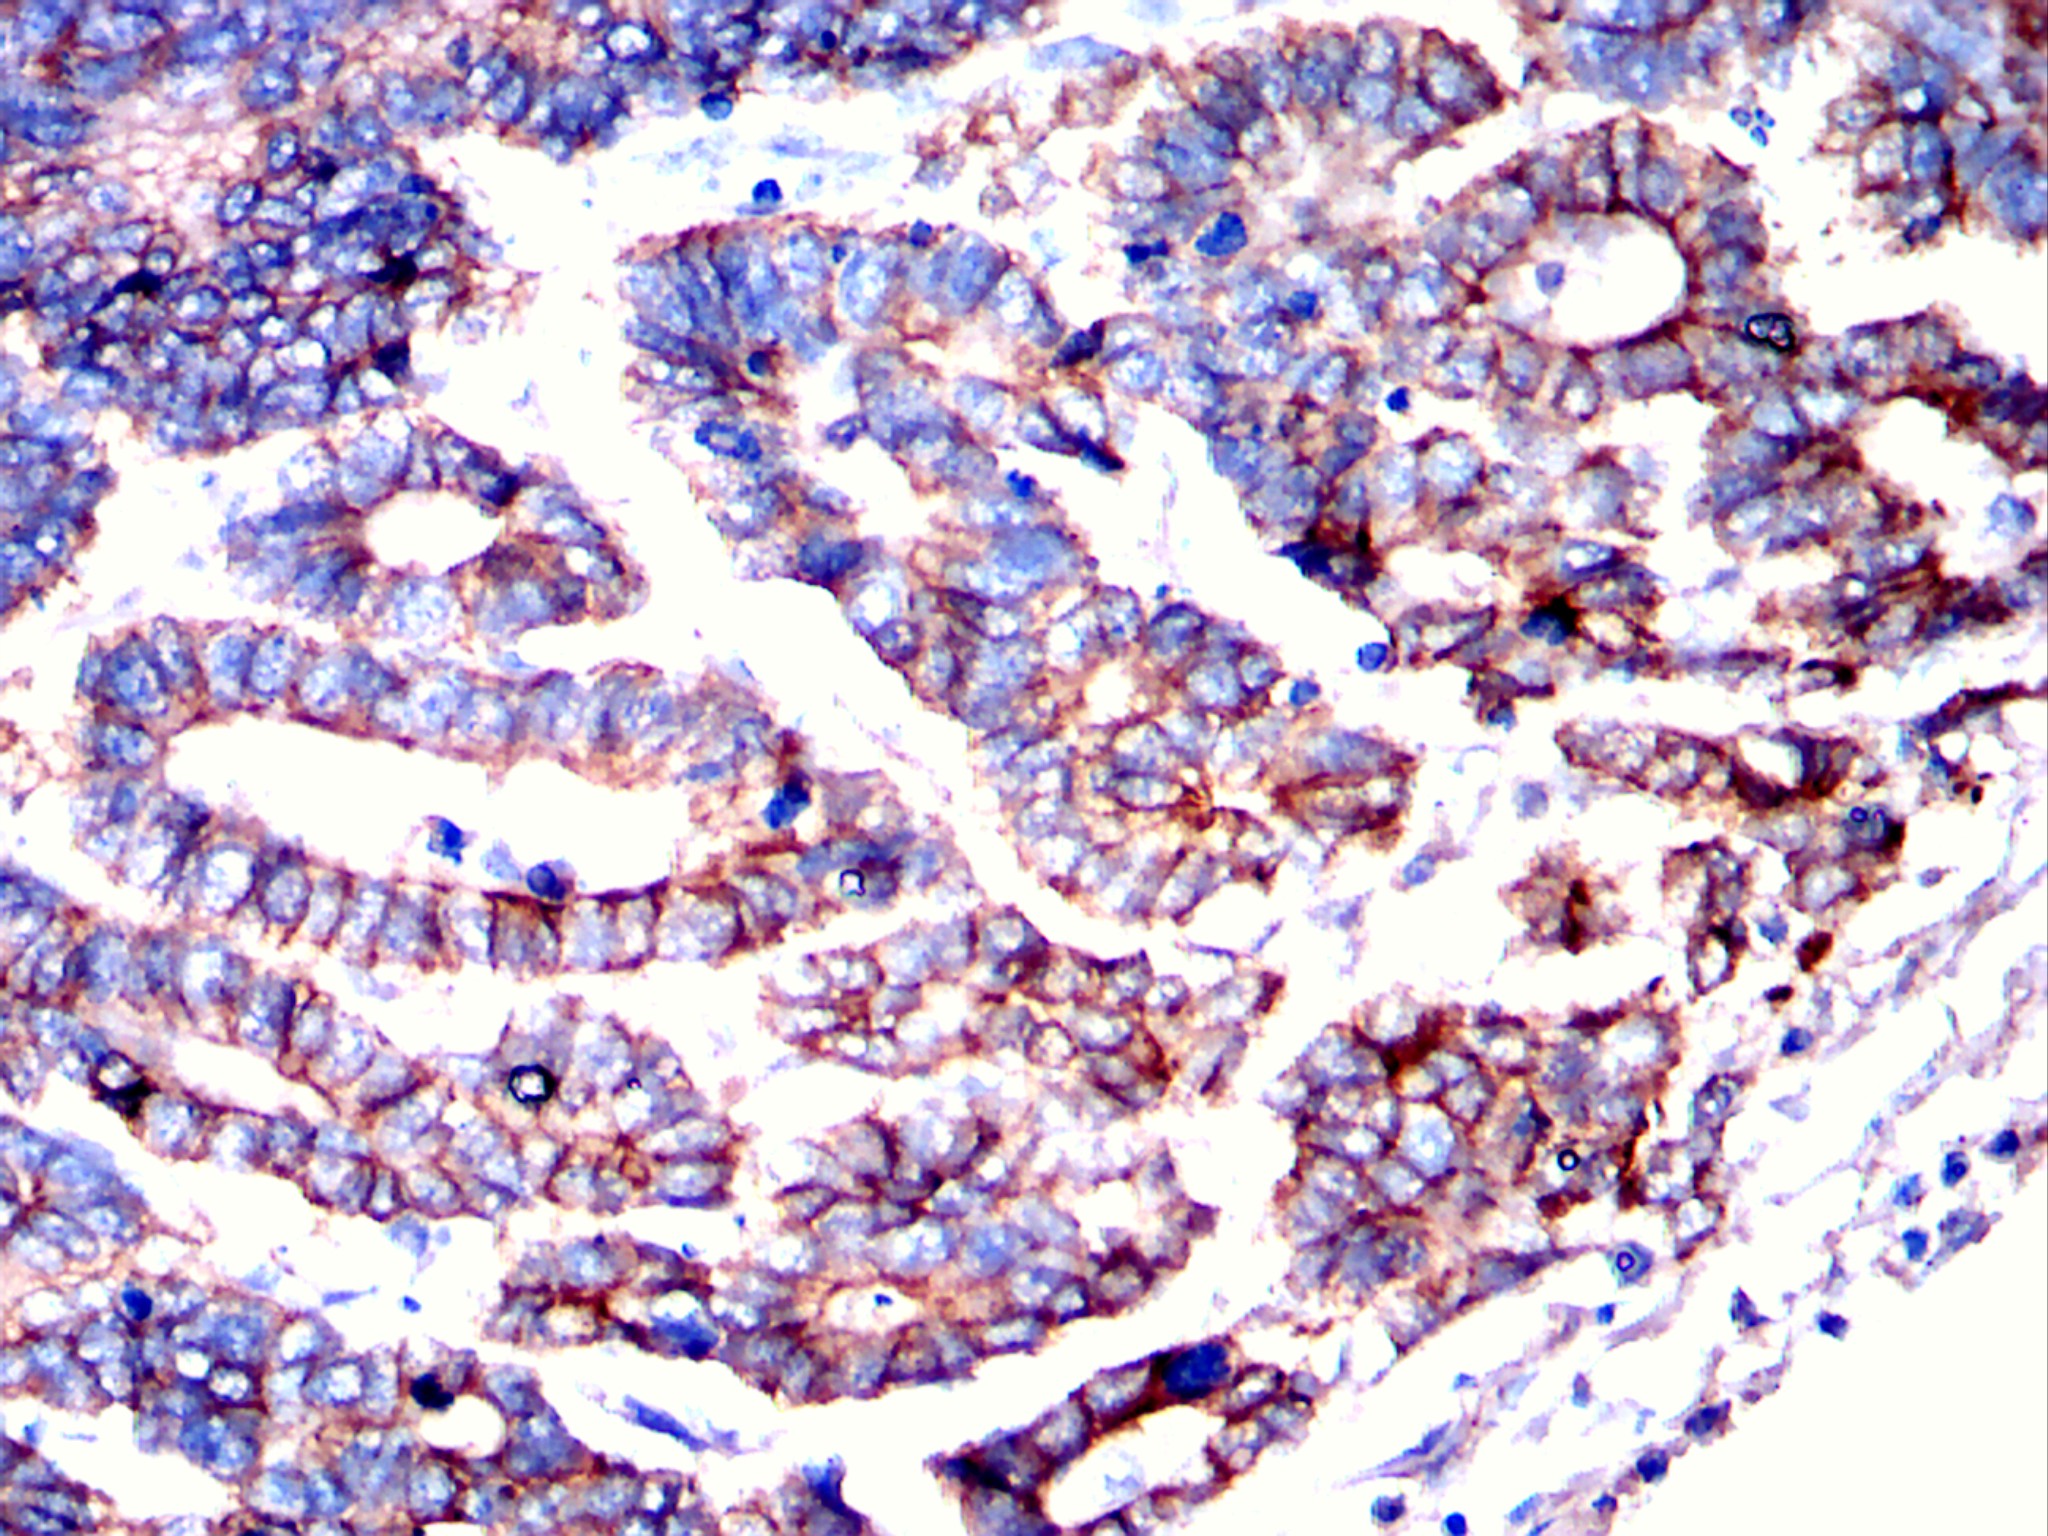

分类: 科研抗体货号: 20297别名: CK19; K1CS; MGC15366; KRT19应用: IHC, IF, FCM反应种属: Human, Mouse, Rabbit